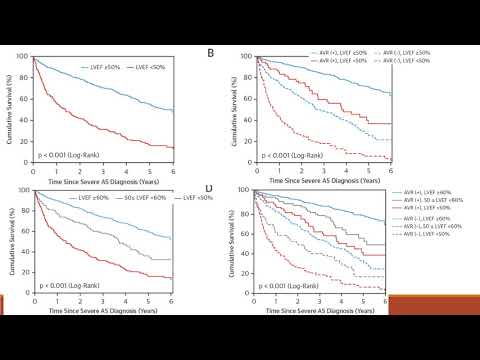

Resultados de pacientes con estenosis aórtica asintomática en clínicas de válvulas cardíacas. Dra. María Laura Estrella. Residencia de Cardiología. Hospital C. Argerich. Buenos Aires

Fracción de eyección reducida en pacientes con estenosis aórtica. Dra. Eugenia Doppler. Residencia de Cardiología. Hospital C. Argerich. Buenos Aires